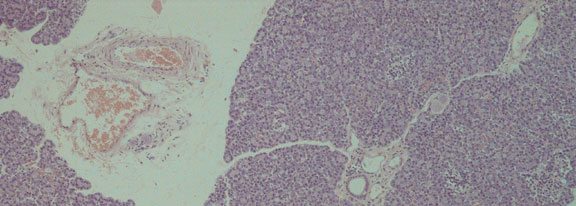

Case 2:

Haematoxylin & Eosin (x100)